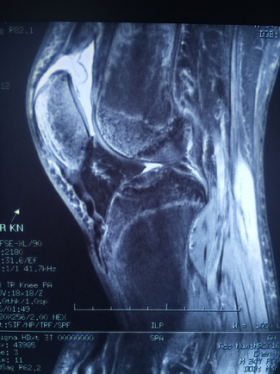

日前,我院运动创伤与关节镜外科针对一例肾移植术后股四头肌腱断裂患者,采取了双侧股四头肌近端重排,股四头肌腱止点重建及自体肌腱加强固定的个性化手术治疗。

患者,男性,35岁,半年前因双肾尿毒症行右侧肾移植手术,围术期发生双侧股四头肌腱病理性断裂,无法站立步行给患者正常生活造成极大不便,但因为手术风险极大,近半年来患者就诊多家医院未果,近日患者就诊于运动创伤与关节镜外科。

股四头肌腱是重要的伸膝装置,断裂后患者无法步行及站立,生活质量受到严重影响,传统股四头肌腱重建需使用大量内植物。徐洪港副主任医师针对该患者特殊体质,与相关科室沟通、会诊及全面的手术方案制备完成后对该患者进行了个性化手术治疗。术中针对患者的特殊情况,不用内植物,而进行骨隧道的方式进行股四头肌腱止点重建,但因患者受伤时间较久,肌腱近端回缩严重,故另取自体半腱肌一根行穿髌骨横向骨隧道进行股四头肌的加强缝合;因左膝肌腱回缩较重,另行了股四头肌肌腱的“Z”形延长术。手术顺利,术中出血不足20ml,术后患者生命体征平稳,已可直腿抬高。